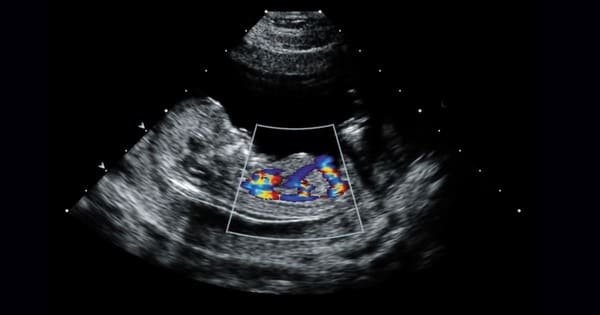

A Fetal Echocardiogram is a specialized ultrasound that examines the structure and function of an unborn baby’s heart. It is typically performed between 18 to 24 weeks of pregnancy.

At Heart Care Clinic, Dr. Amar Upadhyay uses advanced fetal echo technology to detect congenital heart defects early, ensuring proper planning and care before and after delivery.

Dr. Amar Upadhyay provides specialized fetal echocardiography consultations to assess the heart health of unborn babies. Using advanced ultrasound imaging, he evaluates the fetal heart’s structure, valves, and blood flow, helping detect congenital heart defects early. By interpreting fetal Echo results accurately, he guides parents and healthcare teams in planning timely interventions or postnatal care. Dr. Upadhyay explains findings in clear, reassuring terms, ensuring parents understand their baby’s condition and next steps. His expertise and compassionate approach make fetal echocardiography a vital tool for early diagnosis, effective management, and safeguarding the heart health of the unborn child.